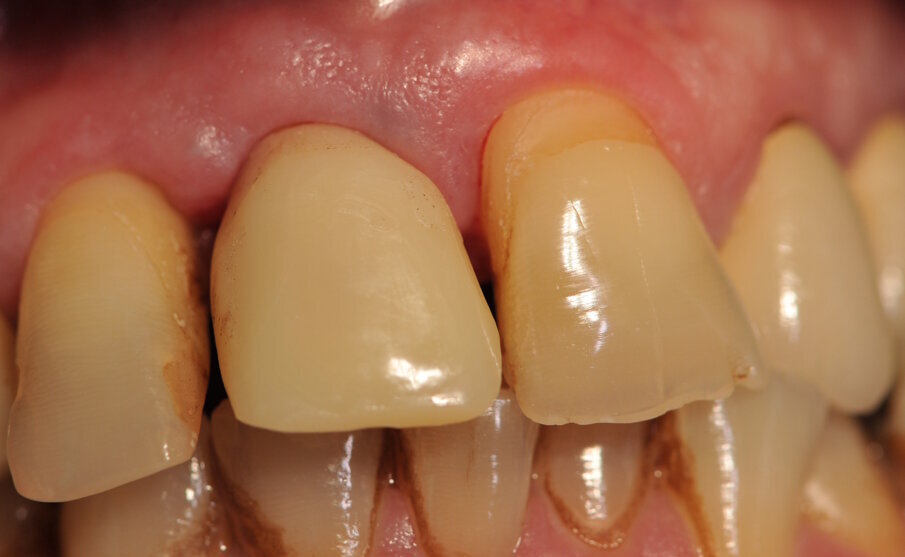

Paziente di sesso maschile di 60 anni di età giunto alla nostra osservazione per una edentulia parziale dovuta all’assenza dell’elemento 1,1. La situazione clinica è resa esteticamente e funzionalmente complicata dalla assenza dell’elemento 2,2 che considerato lo spostamento dei denti contigui comporta un aumentato spazio per la sostituzione protesica dell’elemento 1.1. Si effettua dopo rx di controllo il posizionamento di un impianto osteintegrato GTB diametro 3,6 x 9 mm ,con posizionamento, come da protocollo, 1,5 mm sottocrestale ed inserzione immediata di moncone easy abutment slim 3,4 x 7 mm altezza gengivale 3,5 mm. angolato a 10 gradi (Easy Abutment Slim – GTB Plan1Health Amaro, UD, Italy). Con l’ausilio di una cappetta easy si costruisce e si cementa, con tecnica extraorale, una corona provvisoria in resina acrilica con forma a pontic su elemento 1.1 in modo da eseguire un carico immediato e fornire al paziente una estetica immediata (Figg. 1-3). Dopo 12 settimane ad avvenuta osteointegrazione si provvede all’impronta definitiva eseguita a livello abutment con elastomero di precisione Aquasyl Monophase (Dentsply) e con idonea cappetta easy (GTB Plan1Health Amaro, UD, Italy). La stessa cappetta easy viene utilizzata dal laboratorio odontotecnico come cappetta da sovrafusione garantendo standard di precisione stabiliti industrialmente (Figg. 4-8). La corona costruita in lega preziosa e porcellana viene cementata dopo una settimana, fatte le prove estetiche e occlusali necessarie sul paziente. I controlli a distanza di 4 anni, sia radiografici che clinici, confermano la stabilità dell’osso intorno all’impianto e la mancanza di perdita di tessuto gengivale attorno allo stesso (Figg. 9-11).

Fig. 14_ Corona definitiva a 4 anni dalla cementazione. Notare la stabilizzazione dei tessuti molli.

Impianti e monconi di piccolo diametro soprattutto se dotati di platform switching e con abutment a profilo concavo garantiscono una più elevata performance biomeccanica, consentendo nello stesso tempo il mantenimento dell’osso crestale e dei tessuti gengivali intorno agli stessi. In egual misura questa tecnica permette di mantenere un ottimo livello estetico e una notevole facilità di sviluppo per l’odontotecnico con il vantaggio di avere tutte le connessioni in zona di pulizia o di controllo.